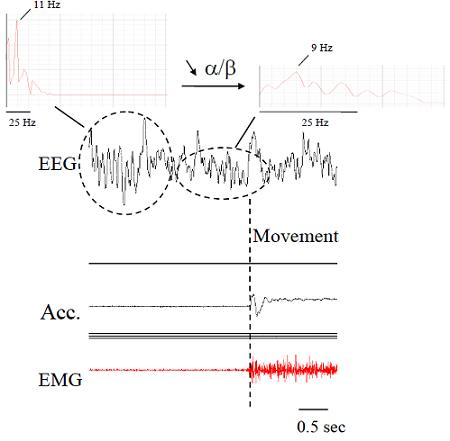

2.1. Electromyography (EMG)

2.2. Accelerometers

3. Methods of Signal Processing for Tremor

3.1. Editing

3.2. Noise Minimization and Wavelets

3.3. Spectral Estimations

| EMG and EEG recordings (time-frequency analysis, coherence, ERS/ERD) |